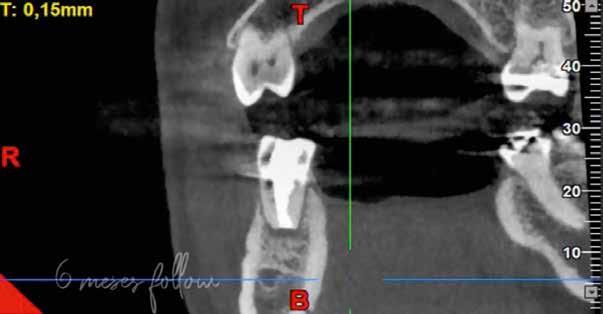

A mesialis gyökér megfelelő endodonciai ellátásának ellen őrzése céljából a pácienst egy kontroll CBCT-felvételre irányítottuk. A felvételen látható volt, hogy az MB2 csatornát teljes terjedelmében ki tudtuk tölteni a sealerrel, továbbá, hogy az apikális harmadban az MB1 és MB2 csatornák között egy keskeny összeköttetés található, valamint hogy az MB1 és MB2 gyökércsatorna különálló végződéssel rendelkezik (14. ábra) . A fogat kompozitfelépítéssel láttuk el, majd visszairányítottuk a beküldő orvosához. Csücsökborítást biztosító indirekt restaurátum készítését javasoltuk, illetve 6 hónap múlva kontrollvizsgálat céljából visszarendeltük magunkhoz. A 6 hónapos kontroll során készített CBCT-felvételen a gyökércsúcsok körül nem voltak gyulladásra utaló jelek. A fog teljesen panaszmentes volt és a Schneider membrán megvastagodását sem észleltük (15. a–b ábra.).

A radiológiai felvételek elemzése során a fog gyökércsúcsának megfelelően radiolucens elváltozást észleltünk, valamint a fognyak területének megfelelően szintén egy radiolucens területet figyelhettünk meg (1–2. ábra). Az elváltozások kiterjedésének és mélységének pontosabb meghatározása érdekében CBCT-felvétel készült (3. ábra). A felvétel alapján Heithersay-féle III. osztályú külső fognyaki gyökérfelszívódást diagnosztizáltunk (Heithersay Class III external cervical invasive root resorption; ECIR). Ezzel egyidejűleg pedig szimptomatikus periapikális periodontitis is fennállt. Ezt követően a pácienst a vizsgálati eredményekről, a kezelési alternatívákról és a várható prognózisról is tájékoztattuk.

A cikkekben bemutatott esetnél a kezelésre szoruló fog gyökércsúcsánál periapikális lézió volt megfigyelhető és ezzel egyidejűleg külső fognyaki gyökérrezorpció is fennállt. A periapikális és a rezorptív lézió méretének pontos meghatározását és térbeli elhelyezkedésének vizsgálatát CBCT-felvétel segítségével végeztük.

A periapikális léziók rezekciót követő gyógyulási hajlamát több faktor is befolyásolhatja. Ezek közül elsősorban a retrográd preparáció mélységét (amelynek minimum 3 mm-t el kell érnie) és a retrográd gyökértömés során felhasznált anyagot emelnénk ki. A beavatkozás óta eltelt idő is hatással van a gyógyulás aktuálisan megfigyelhető stádiumára. Minél hosszabb idő telt el a beavatkozás óta, potenciálisan annál teljesebb körű csontos telődésre számíthatunk. Ebben az esetben az obszervációs periódus során több CBCT-felvételt is készítettünk, hogy végig tudjuk követni a gyógyulás folyamatát. A kezelés során a fogat szándékosan eltávolítottuk, majd a rezorpciós üregben lévő granulációs szövetet kikürettáltuk és a megtisztított felszíneket 90%-os triklór-ecetsavval fertőtlenítettük. Az így előkészített üreget hidrofil tulajdonságokkal rendelkező dual kötésű nano-hibrid resintartalmú ionomer cementtel töltöttük fel (Geristore, DenMat; 4. ábra).

Ezt követően a gyökércsúcsot extraorálisan rezekáltuk, majd a gyökércsatornát retrográd irányból ultrahangos eszközök segítségével 3 mm mélységben feltágítottuk (EndoSuccess apikális sebészeti készlet, EndoSuccess apical surgery kit; ACTEON). A retrográd gyökértömést ásványi trioxid aggregátum (mineral trioxide aggregate, MTA) felhasználásával végeztük (CeraPutty, Meta Biomed), majd replantáltuk a fogat. A visszahelyezést követően szemi-rigid sín segítségével stabilizáltuk a fogat, amelyet 4 hét elteltével távolítottunk el (5. ábra). A beavatkozásokat követően 6 hónappal a gyógyulás ütemének ellenőrzése érdekében kontroll CBCT-felvételt készítettünk. A felvételen a terület maradéktalan regenerációja volt megfigyelhető, a periapikális lézió szinte teljes mértékben telődött (6. ábra). A szájüregi állapot is megfe-

ábra: A 6 hónappal később készült kontroll CBCT-felvételen a periapikális lézió szinte teljes körű gyógyulása volt megfigyelhető.